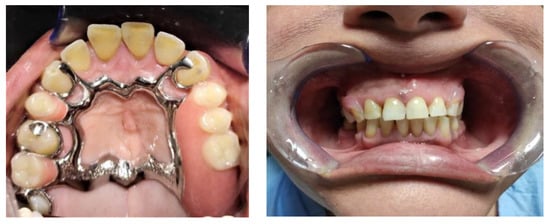

The second impression was used to create a model on which the removable partial denture (RPD) was drawn and realized. In the analog procedure, the model (plaster type IV) was duplicated to create a second model made of refractory material (Figure 10) to be used as a base for the removable partial denture (Figure 11). Lost wax casting was then performed (Figure 12), and finally, the clasps made of nylon were realized (Figure 13).

In the hybrid procedure, the second analog model was scanned using a laboratory scanner (Neway Open Tech 3D) to create the correspondent digital model, then the CAD modeling of the removable partial denture (RPD) was realized (Figure 14). The selective laser melting machine was then connected to the computer to realize the skeleton structure through the application and the melting of hundreds of chrome–cobalt dust layers (Figure 15). The structure was finalized by applying some aesthetic clasps made of nylon (Figure 16).

Figure 12. Chrome–cobalt structure.

Prosthesis 03 00038 g012

Figure 13. Structure with nylon clasps.

Prosthesis 03 00038 g013

Figure 16. Complete structure with frontal clasps in nylon.

Prosthesis 03 00038 g016

Figure 19. Finished and polished prosthesis realized with the analog procedure.

Figure 20. Finished and polished prosthesis realized with the hybrid procedure.